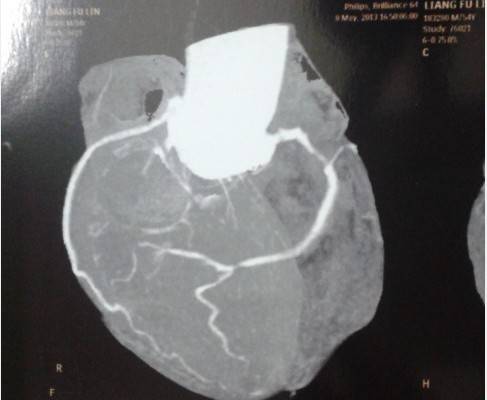

5月初的时候,爸爸突然晕了过去,送去医院检查说是冠心病,说是比较严重了,医生建议动手术。也做了核磁共振和多排螺旋CT检查。

问题出在前降支的中-重度狭窄,有条件的话还是做手术,如果发生了心梗,就麻烦了。如果不做手术,严格按照冠心病的治疗规律服药,不要间断。

前降支近段严重的狭窄病变,挺危险的,还是早点做冠脉造影啊!冠脉介入治疗挺成熟的技术啦